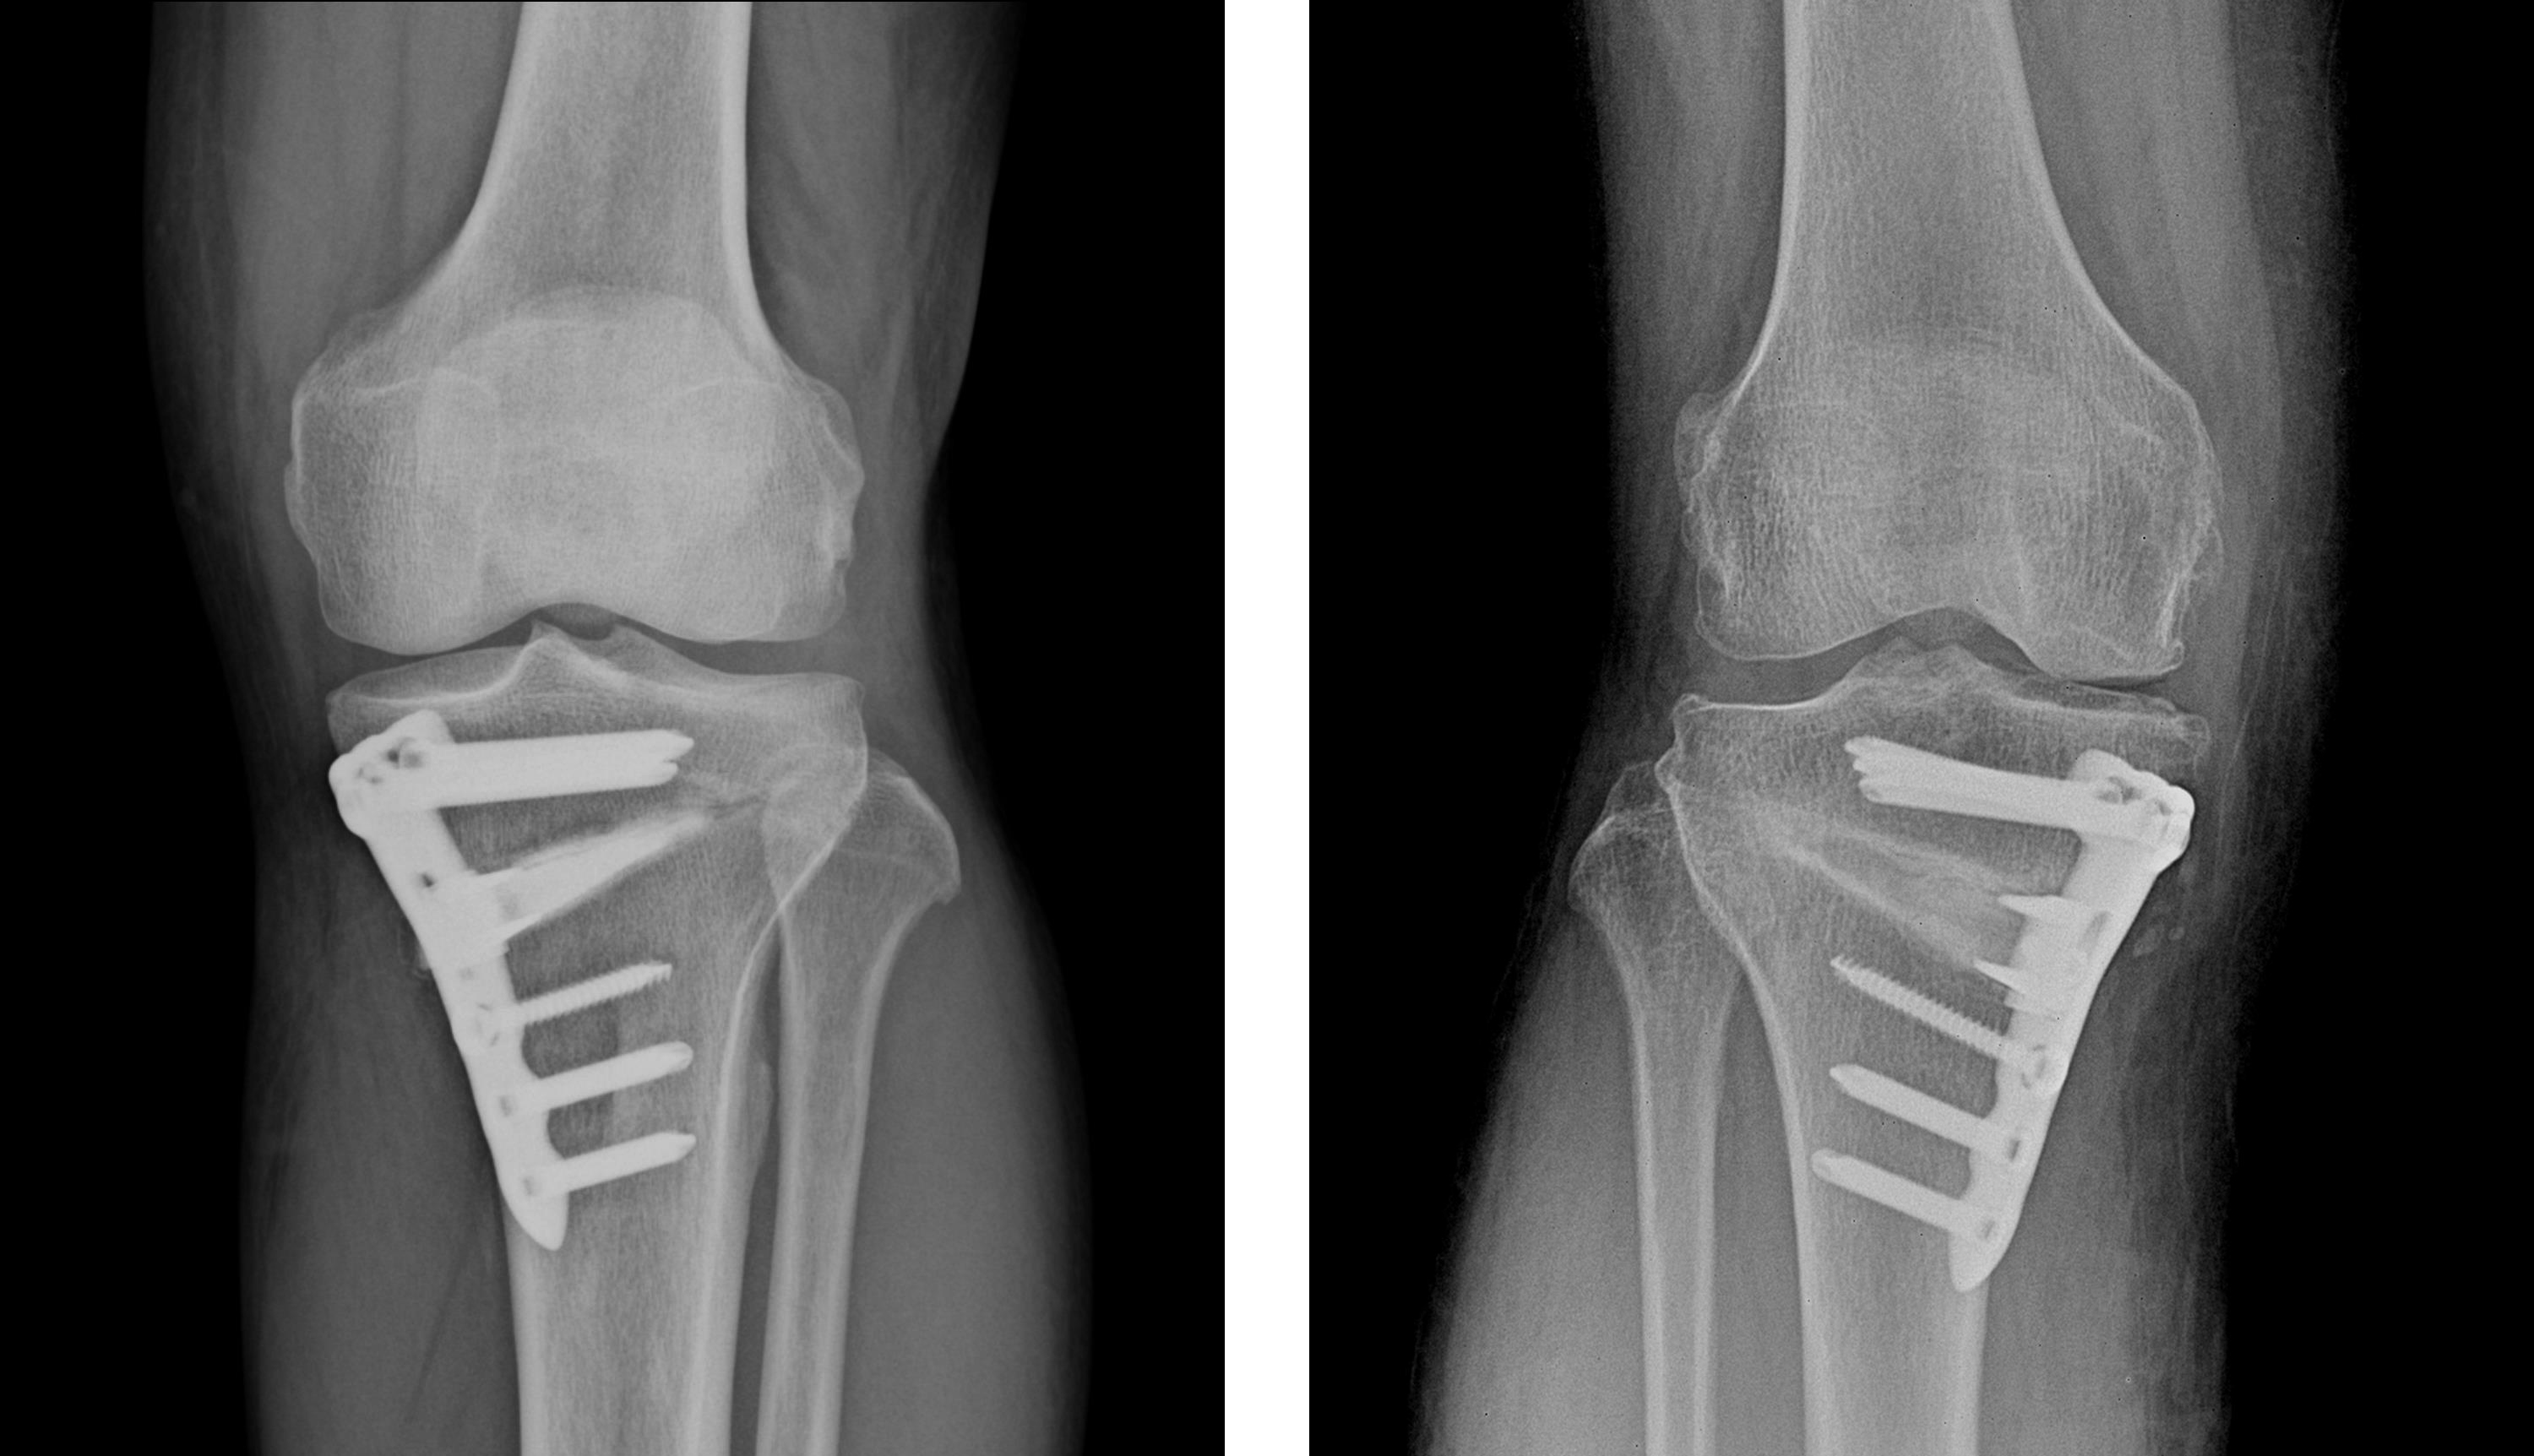

흰다리교정수술(절골술)

관절 연골 손상이 심한 경우 인공관절수술, 관절내시경수술, 연골판재생술, 절골술, 줄기세포치료술 등의 수술적 치료를 시행합니다.